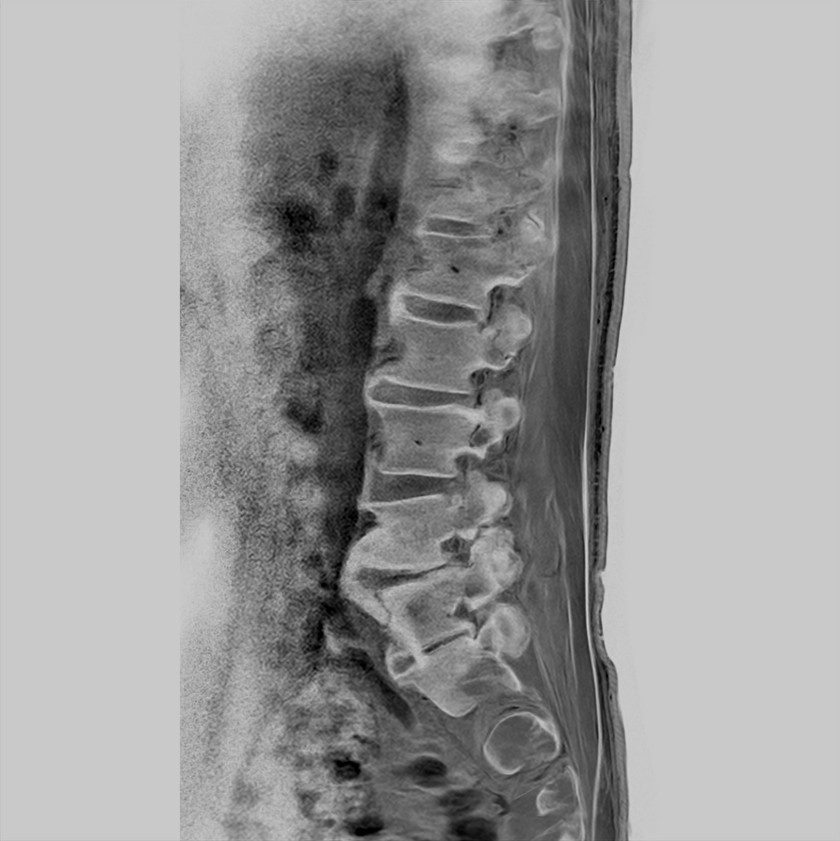

Sagittal T1w TSE